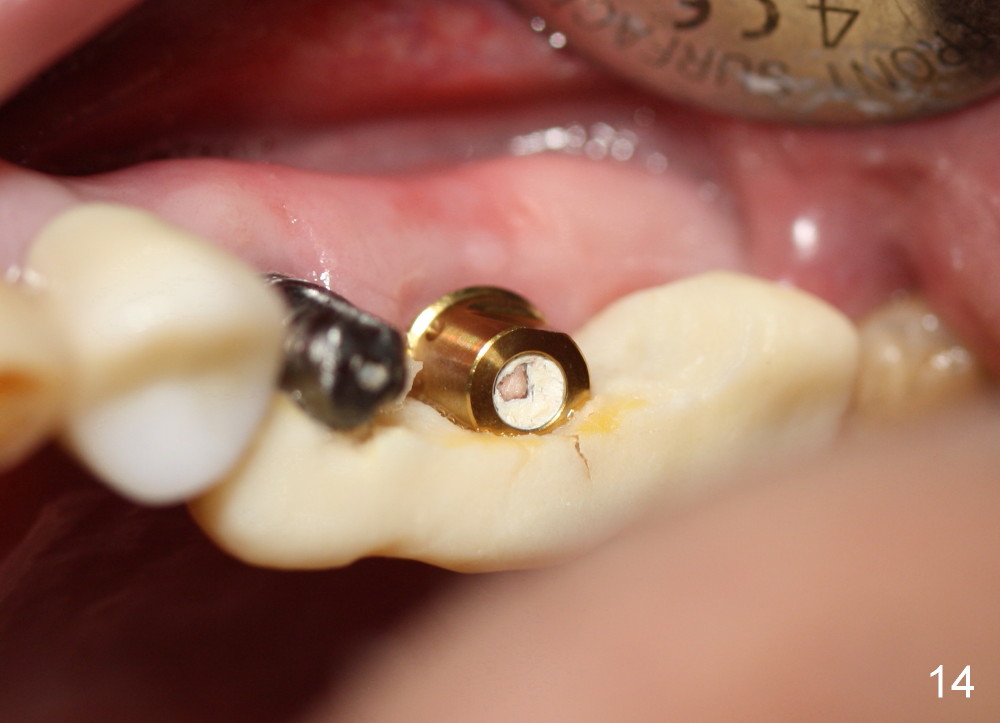

In fact this senile patient unintentionally uses the provisional as a permanent restoration and chews bone on the left side, since at the same time implants at the sites of #29 and 30 are not restored.  Two and a half months post implantation at #13 and 15, the patient returns because the provisional has fractured (Fig.14), while all of the 3 implants are stable with sign of osteointegration (Fig.13).  The patient requests early final restoration, which is honored.  After fabrication of a new temporary bridge, he eats like a dog!